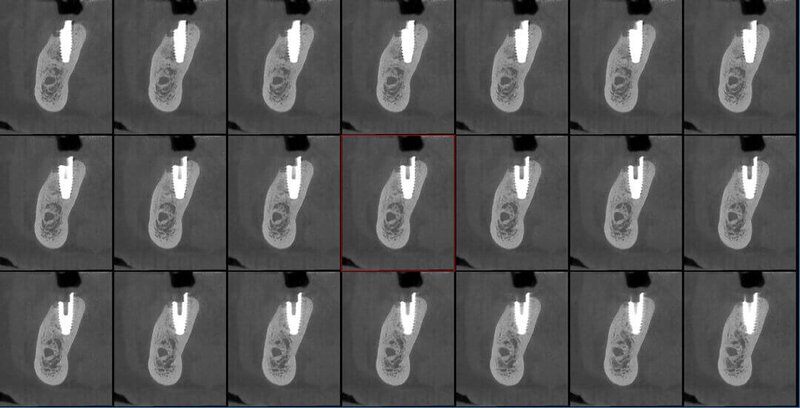

Newtom VGi evo ofrece una gama completa de FOV para la adquisición de volúmenes 3D nítidos y detallados, por lo que se adapta a cualquier necesidad clínica. La selección del campo de vista permite optimizar la región anatómica analizada garantizando un imaging de alta calidad con la mínima dosis posible.

En las exploraciones más avanzadas, los modos Boosted y Enhanced ofrecen la posibilidad de obtener imágenes con el máximo nivel de detalle y calidad, sin concesiones. Disponible para FOV de hasta 15x5 cm, el modo HiRes es ideal para el estudio de áreas anatómicas circunscritas con altísima definición.